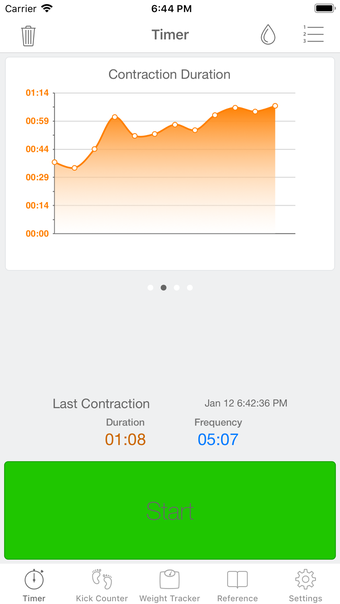

이 어플리케이션은 조기 분만을 겪는 여성들이 분만 과정을 지속적으로 추적할 필요가 있는 경우에 디자인되었습니다. 기능성을 희생하지 않고 사용자 친화적인 어플리케이션을 만들고자 했습니다.

이 어플리케이션은 분만 진행 상황을 명확하게 보여주며, 현재 분만 단계, 이전 및 현재 수축의 시작 및 종료 시간을 보여줍니다. Full Term은 수동으로 각 수축을 시작하고 중지할 필요가 없으며, 어플리케이션을 재시작하더라도 분만 기록을 추적합니다.